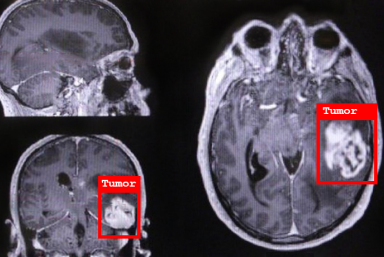

- Disease Detection, Diagnosis, and Treatment

Empower precise diagnostics, personalized treatments, and streamlined medical workflows by leveraging advanced imaging and machine learning technologies.